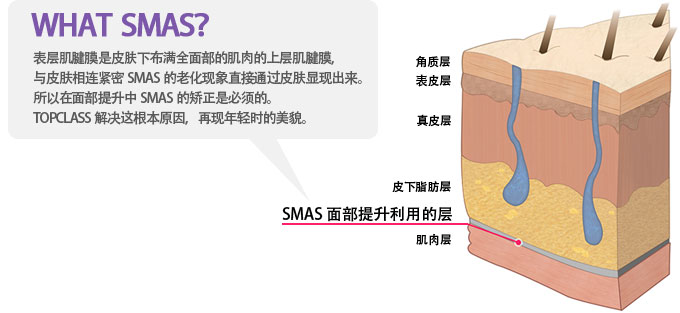

沿着耳上头发内

侧到耳前侧,

后侧的褶皱切口切开的部位到SMAS

层剥离,分离并去除

松垮的组织。使用特殊的线,

提拉皮肤下的SMAS

面部肌肉层,固定后将多

余的皮肤切除并缝合。